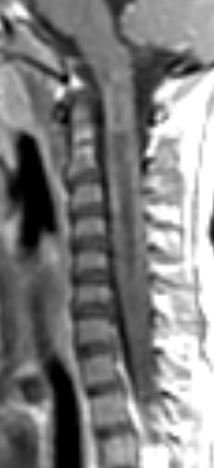

Tip of the day 💡: Heterogeneous, expanded, enhancing along the margins, much edema....yes, agree!...but worth checking AQP4 antibody status- might save the child a biopsy or debulking surgery! Brain and optic nerves were normal in this case. Final diagnosis: AQP4-neuromyelitis.